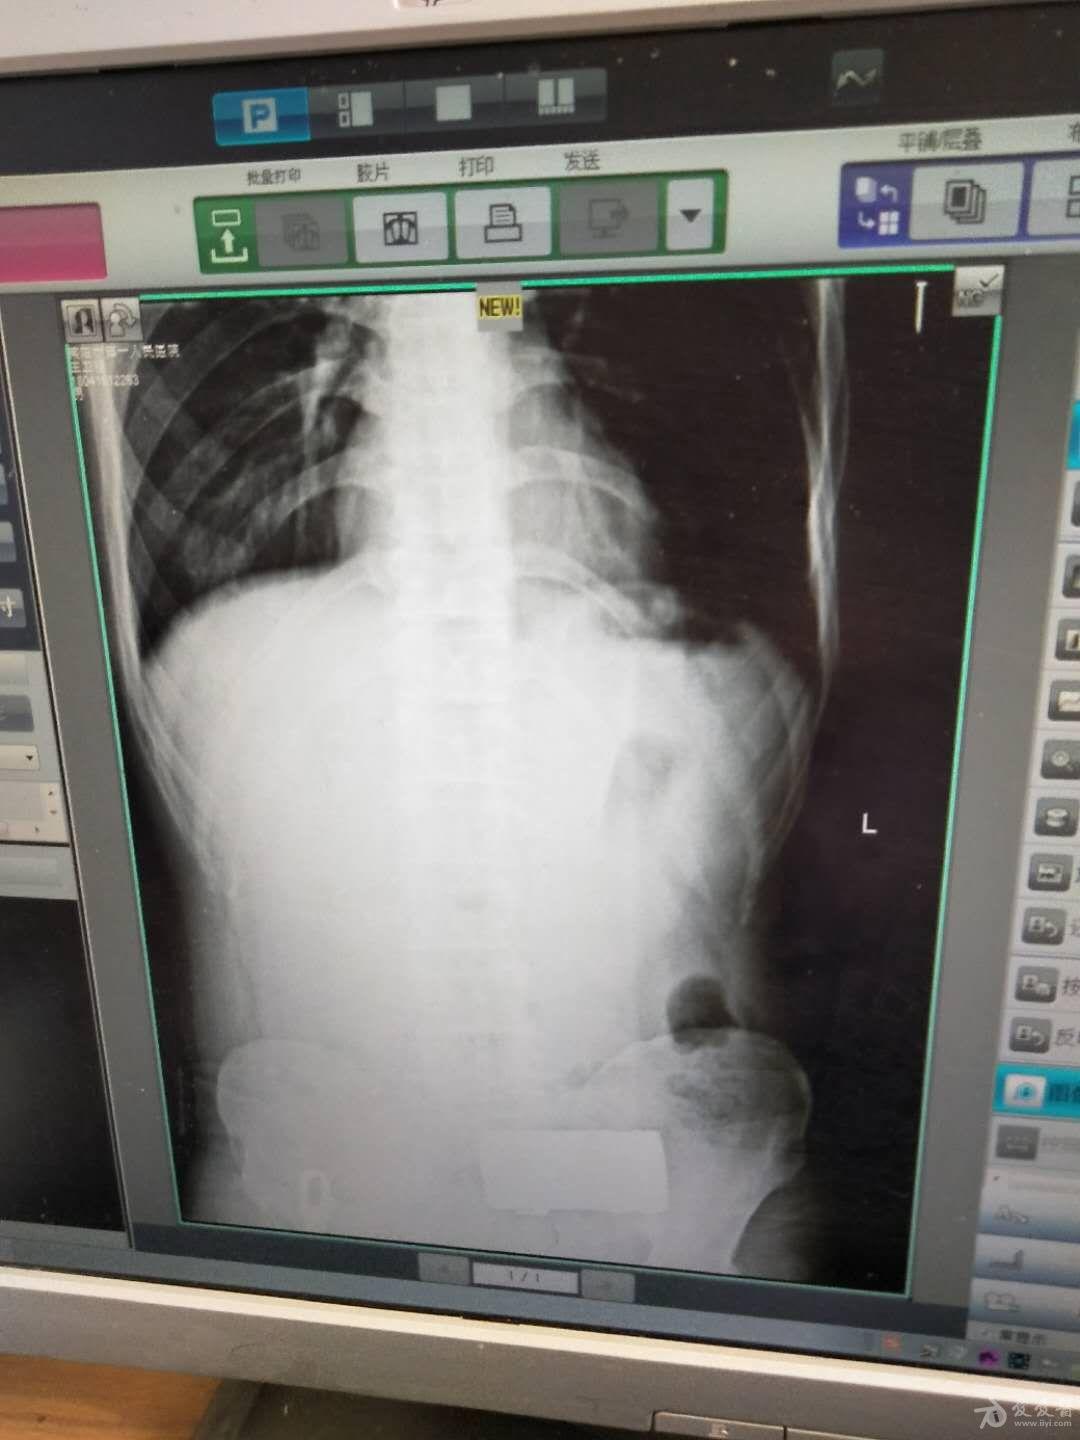

视觉冲击肠梗阻

图片尺寸768x576